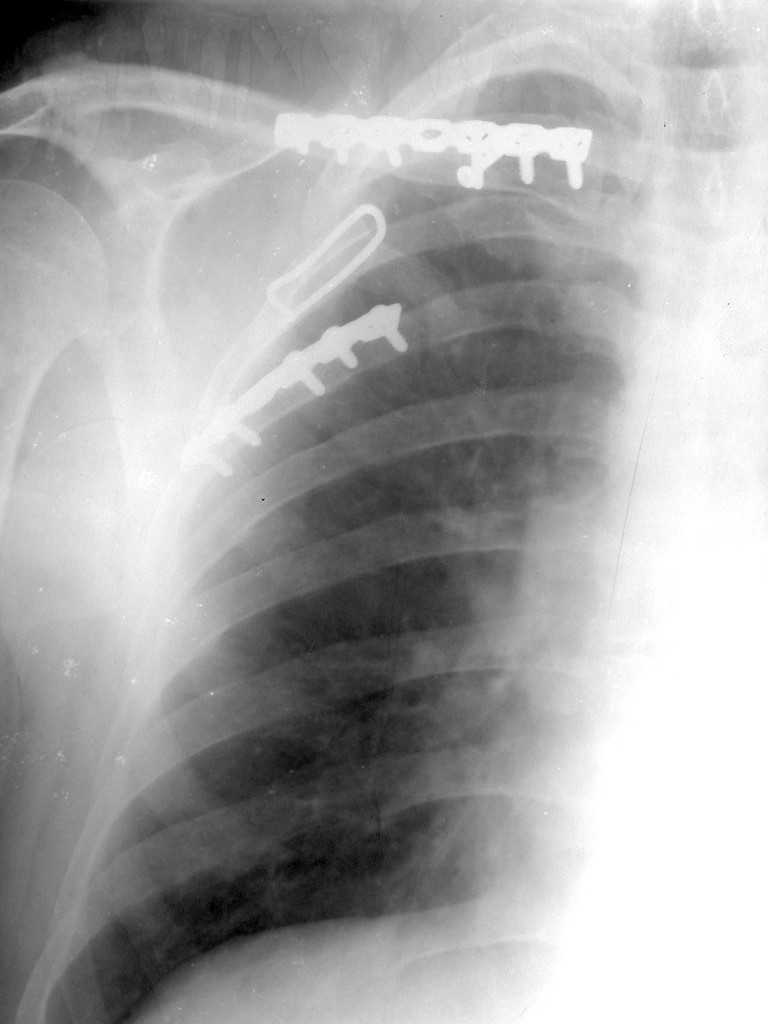

Re: Перелом лопатки, ключицы, ребер

К сожелению доктор который занимается грудной клеткой в отпуске, у себя нашёл только вот этот снимок